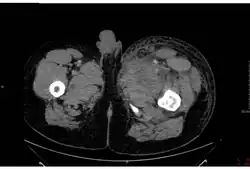

.jpg)

Cutaneous anthrax, also known as hide-porter's disease, is when anthrax occurs on the skin. It is the most common (>90% of cases) and least dangerous form (low mortality with treatment, 23.7% mortality without).[21][5] Cutaneous anthrax presents as a boil-like skin lesion that eventually forms an ulcer with a black center (eschar). The black eschar often shows up as a large, painless, necrotic ulcer (beginning as an irritating and itchy skin lesion or blister that is dark and usually concentrated as a black dot, (somewhat resembling bread mold) at the site of infection. In general, cutaneous infections form within the site of spore penetration two to five days after exposure. Unlike bruises or most other lesions, cutaneous anthrax infections normally do not cause pain. Nearby lymph nodes may become infected, reddened, swollen, and painful. A scab forms over the lesion soon, and falls off in a few weeks. Complete recovery may take longer.[22] Cutaneous anthrax is typically caused when B. anthracis spores enter through cuts on the skin. This form is found most commonly when humans handle infected animals and/or animal products.[23]